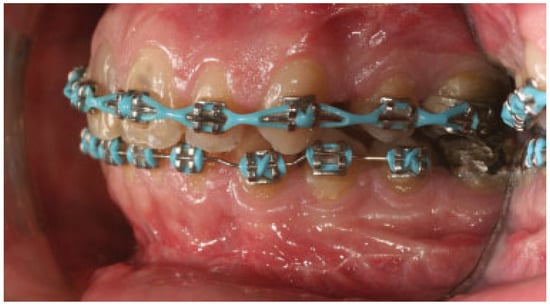

:Case Report